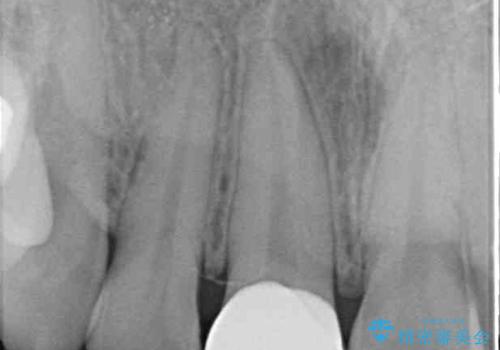

- 結婚式を前に、保険診療での前歯のクラウンが気になるとのことで来院された患者様です。

色合いだけでなく、歯肉の縁が黒くなっていることが分かります。

速やかに仮歯に交換し、オールセラミッククラウンにて補綴することとしました。

神経組織が健全な状態で残っている歯であったため、1ヶ月かからずに治療を終えることができました。